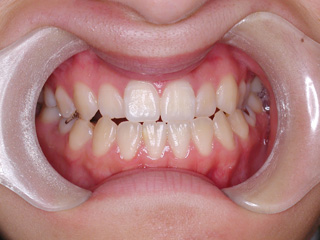

主訴:受け口

診断名:下顎左右第二小臼歯先天欠如、下顎左方偏位を伴う下顎前突

年齢:14歳

下顎の第二小臼歯の先天欠如が見られました。先天性欠如歯がある場合、上下顎小臼歯抜歯のスタイルで歯数を合わせる事も多いのですが、抜歯数が増えるのが難点です。 プロファイル、下顎前突、非対称の問題を考慮して下顎にオーソアンカー SMAPシステム を植立し、下顎晩期残存の乳歯のみを抜歯し、永久歯の抜歯は行わず空隙を閉鎖致しました。大臼歯の咬合についてはIII 級仕上げ という噛み合わせにしています。